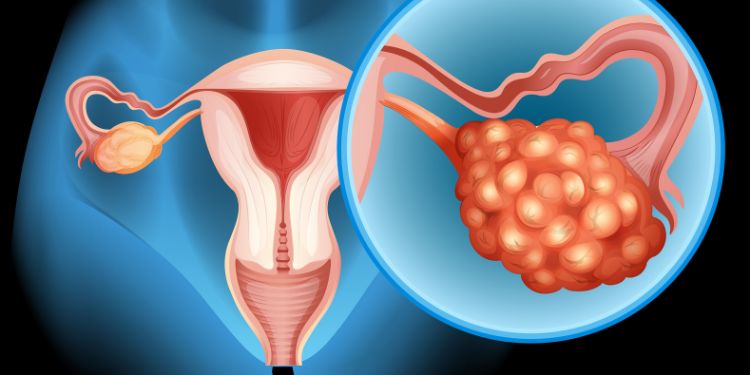

Advancing Embryonic Development: Journal of Embryology is the venue for sharing your groundbreaking research in the field of embryonic development, Developmental Biology, Stem Cell Research, Genetic and Epigenetic Mechanisms, Reproductive Medicine, Embryonic Pathology, Organogenesis and Morphogenesis.